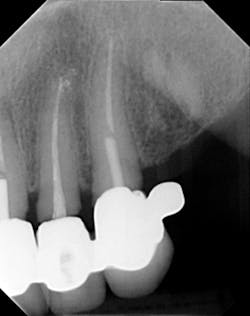

Dentition: Upper anterior splinted crowns had open margins and caries. Radiographs confirm decay, along with open margins (figures 6–11). Lower incisal anterior wear noted (figure 2).

Periodontium: Probing depths normal on all teeth, with some bleeding noted around the margins of the upper splinted crowns. Slight to moderate bone loss on lower anterior teeth.